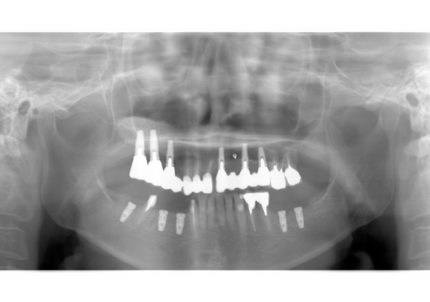

↑2006年4月24日

↑2008年12月

↑2006年4月24日(初診時)

↑2024年6月26日